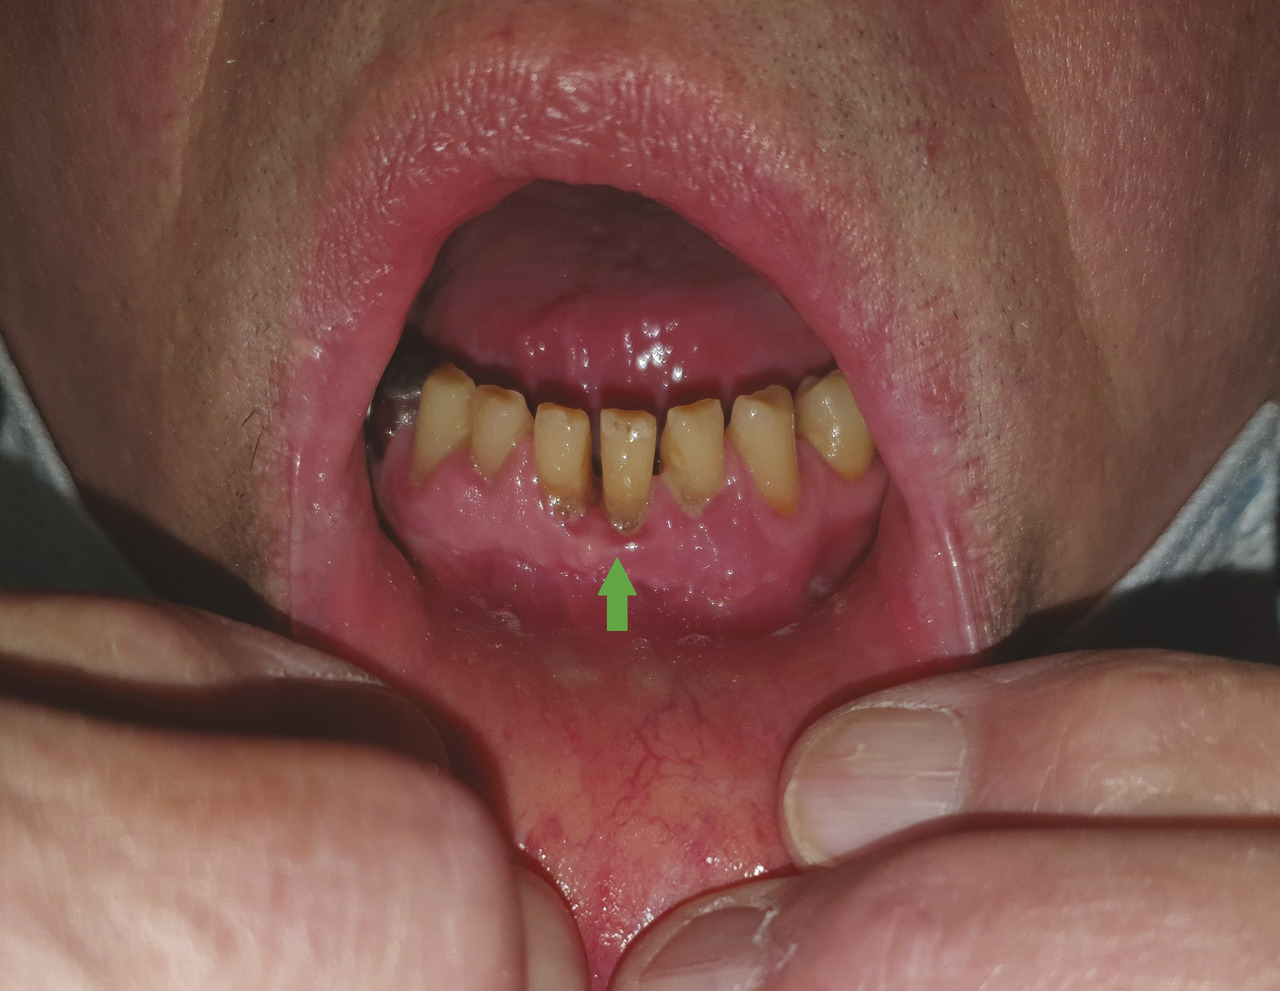

Jacques-Marie, 64 ans, consulte pour des douleurs dentaires importantes. L’examen clinique révèle des ulcérations interdentaires (figure), et l’interrogatoire des arthralgies. En outre, une uvéite a été diagnostiquée la semaine précédente par un ophtalmologue.

Cliniquement, l’atteinte gingivale peut être la première manifestation clinique de la maladie ; elle se caractérise par des ulcérations pouvant s’accompagner d’une lyse de l’os alvéolaire – semblable à celle observée dans l’ostéite de Perthes-Jüngling (géodes osseuses sans atteinte du périoste) – évoluant vers une mobilisation des dents.